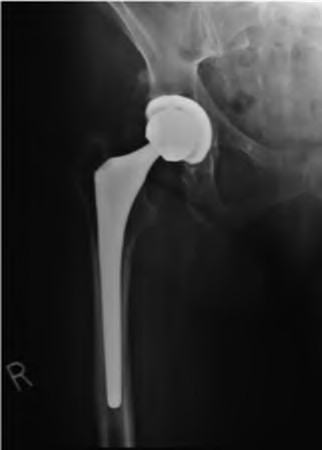

Question 9:

A 55-year-old highly active man is scheduled for a total hip arthroplasty (THA). The surgeon considers utilizing a ceramic-on-ceramic bearing surface to maximize longevity. Which of the following is the most notable disadvantage or complication specific to a ceramic-on-ceramic bearing compared to ceramic-on-highly cross-linked polyethylene?

Correct Answer: Audible squeaking during hip articulation

Explanation:

Ceramic-on-ceramic (CoC) bearings offer the lowest wear rates of all THA bearing couples and do not cause significant osteolysis or metal-related hypersensitivity. However, a well-documented unique complication of CoC bearings is audible squeaking during motion, occurring in up to 10-15% of patients in some series, often associated with micro-separation or impingement.